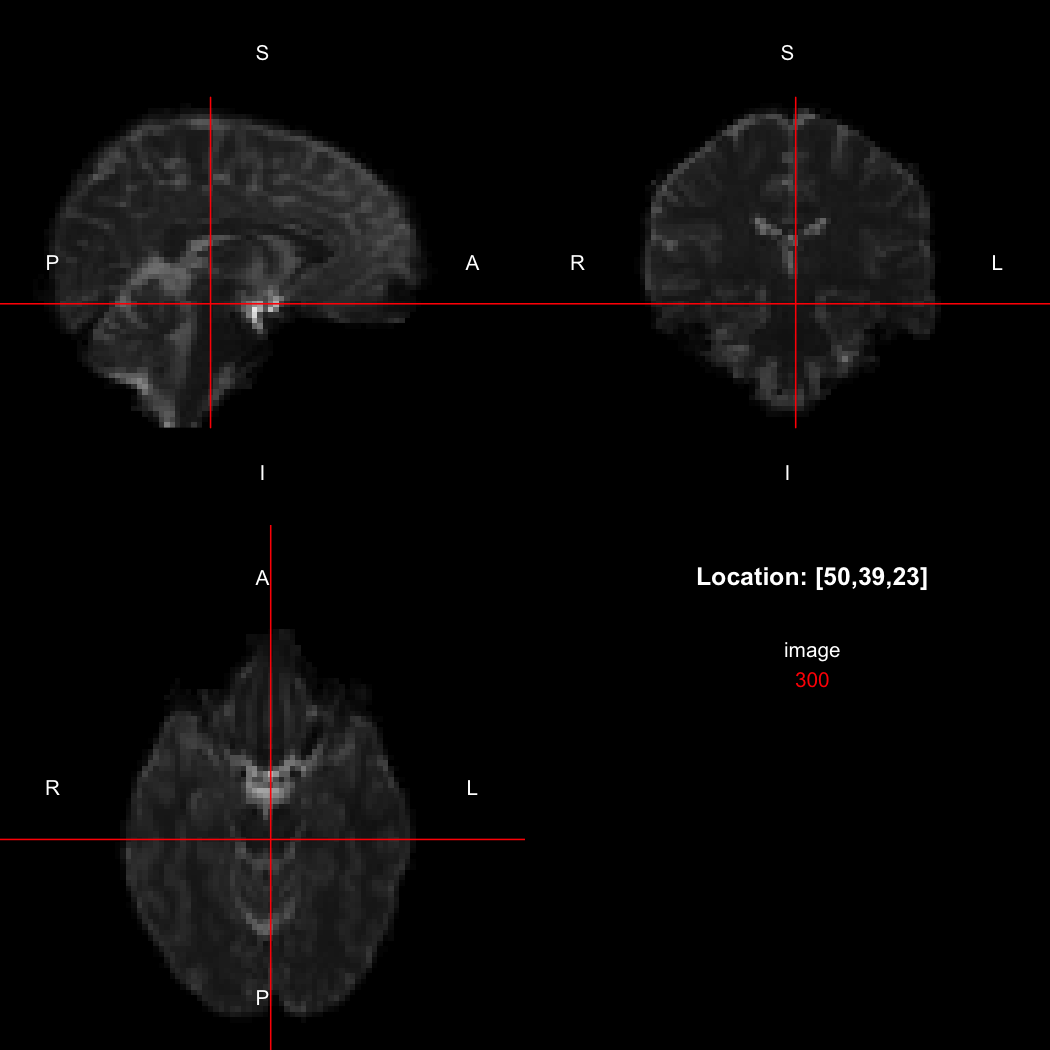

The package contains a basic image viewer, which can be used interactively or noninteractively to examine 2D or 3D images.

view(image)

plot of chunk unnamed-chunk-5

By default, the viewer shows labels indicating image orientation, crosshairs pinpointing the currently selected location, the numerical indices of the current location, and the value of the image at that location. Options allow each of these to be turned off, for the content of the bottom-right panel to be customised entirely, for the colour scale to be changed, and for additional images to be layered on top of the base image. See ?view for details.

So, here, “LAS” means that the positive x-axis points left, the positive y-axis anterior and the positive z-axis superior. This is the so-called “radiological” orientation convention, and can be requested when viewing images for those who are used to it:

view(image, radiological=TRUE)

plot of chunk unnamed-chunk-12

Notice the left (L) and right (R) labels, relative to the view shown above. Setting the radiologicalView option to TRUE will make this the default for all future views.

image[50,39,23]

## [1] 300